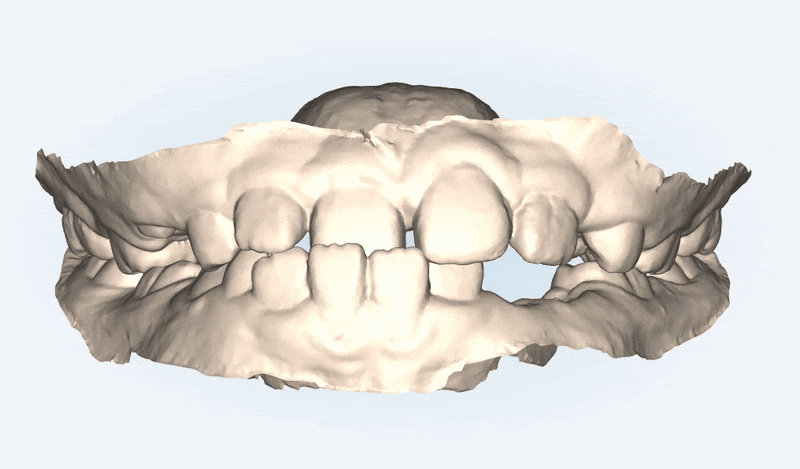

1st Clincheck(30개)

첫번째 클린체크에는 30개의 인비절라인장치로 진행해드렸습니다.

클린체크대로

악궁이 확장되며 점차 정상적인 교합으로 변화되었습니다.